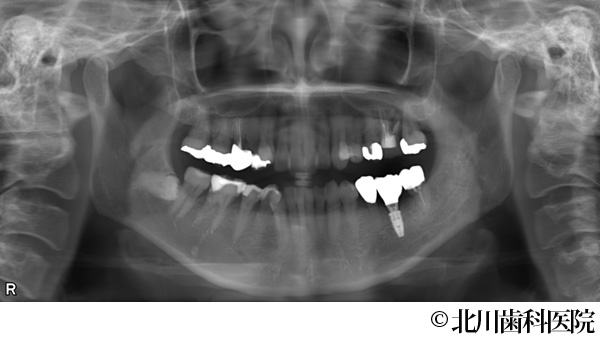

【症例1】インプラントと自家歯牙移植にて機能回復を行った症例

- 治療後

- インプラントと自家歯牙移植にて機能回復を行った症例

- 737,000円(税込)

- 1年3ヵ月

- 女性・50代

左下の奥歯が腫れて痛みがあり、抜歯後にインプラントを希望されて来院されました。

左下の奥歯は2本分の歯を喪失することになるため、抜歯する予定の歯の一つ手前にインプラントを埋め込み、抜歯部には親知らずを移植しクラウン(被せ物)を装着することで対応しました。

インプラントと移植歯により喪失した歯を補うことができ、審美面・機能面の回復につながりました。また、インプラント埋入と同時に移植を行うことで手術が一度に終わり身体の負担を軽減して行うことができました。